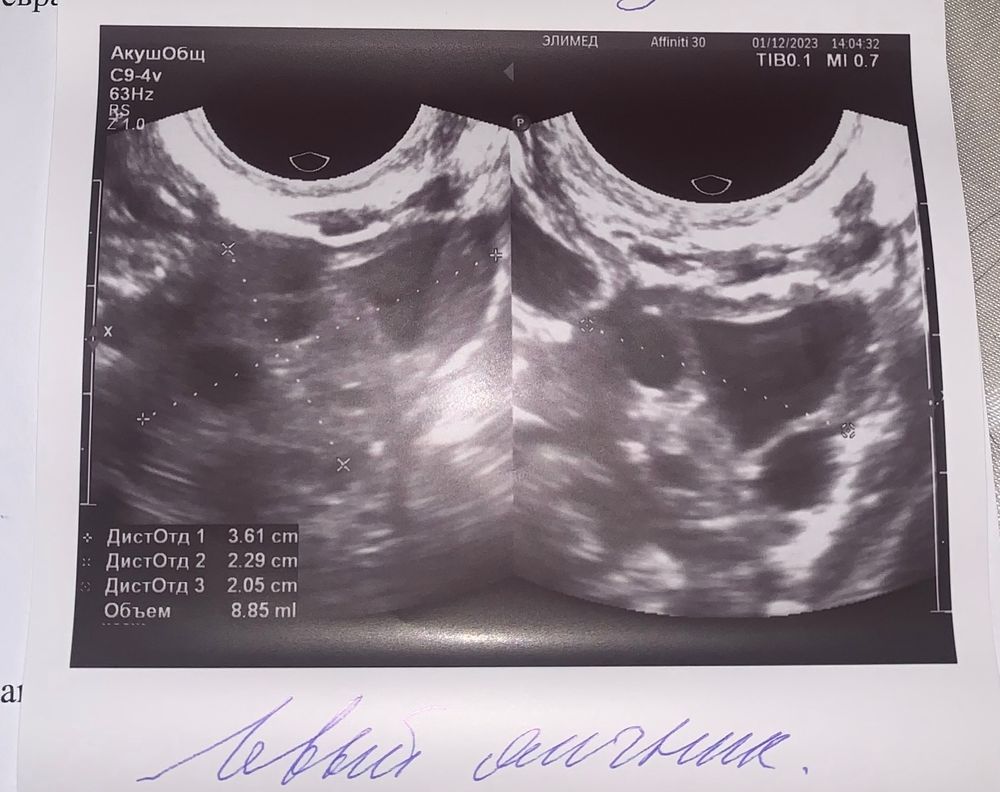

Элис , и если это желтое тело,оно маленькое 12мм всего.Вам надо сдать прогик на 5-7дпо чтобы посмотреть хватит ли прогестерона для прикрепления и далее.